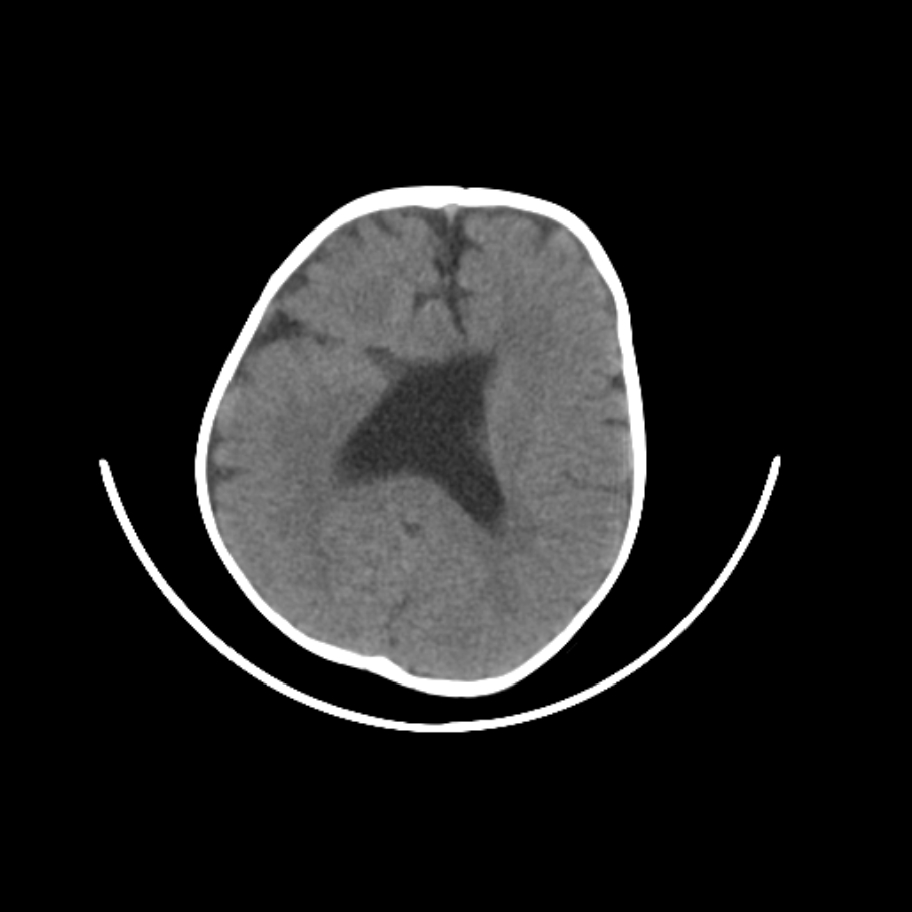

以下是引用随光逐影在2009-4-8 7:51:00的发言:[br]1)透明隔缺如(视-隔发育不良?)。2)右侧脑裂畸形。3)右侧幕上半球脑萎缩。